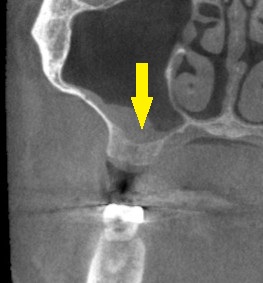

骨の状態を詳しく調べるために、CTを撮影してみると、骨の幅は十分ですが、高さが4~5mmと少なめでした(下の写真、2段目)。

以前なら、ソケットリフトという人工骨を使用した小さな骨造成を併用してインプラントの埋入を行なっていましたが、現在はワイド径のインプラントを使用することで、人工骨を使用しないで埋入を行ないます。